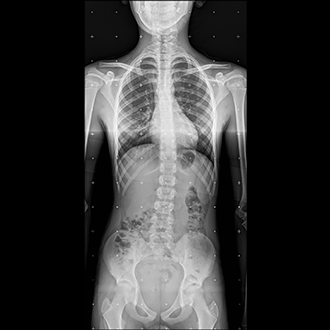

FLFS (Full Leg Full Spine)

This is also called Full Leg Full Spine X-ray system.

This is an integrated system where long segment x-rays of skeletal system are generated.

The x-ray of intended area, viz. whole spine or whole leg are taken together and stitched and printed onto a single film.

This is of great used in pre operative X-rays in certain orthopaedic areas.

We use a dedicated software based measurement system which takes care of most of the needs of orthopaedic surgeon.